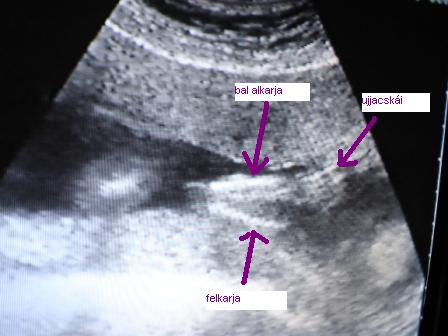

Milyen 35%-hoz kell tartoznom?Jajj ne ilyessz meg,de azért most már légyszi írd le mire gondoltál.Egyébként csütörtök óta 3 doki csinált Uh-ot és a baba jó helyen van és dogog a szíve és kb 2 cm.Én úgy tudom,remélem,hogy ez jó.Csak az a gond,hogy ahány UH annyi adat.Egyébként örülök,hogy ennyire várod az újabb próbálkozást és nagyon drukkolok,hogy mielőbb beköltözzön hozzád egy egészséges pocaklakó.Én nem tudom,hogy ilyenkor mennyit kell várni,de azért tényleg jobb,ha hallgatsz a dokira.Remélem úgy fogysz járni,mint Ági.